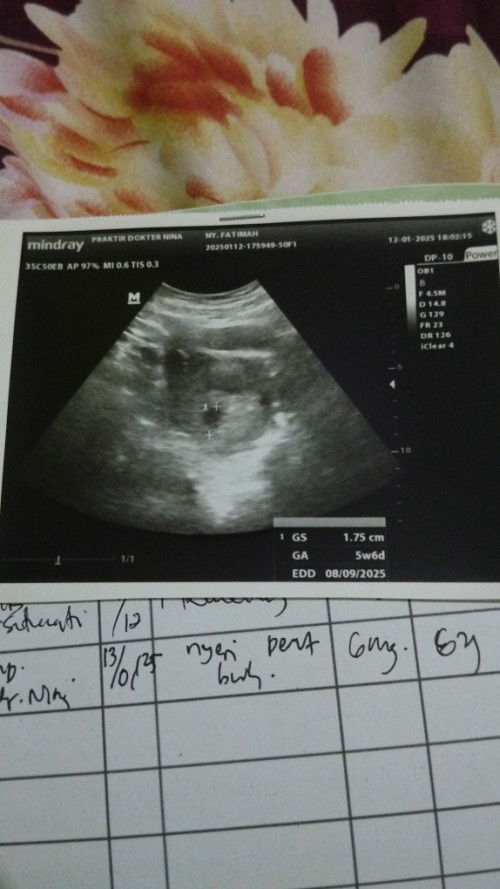

Ada yang punya pengalaman ikat tuba falopi gak disini ? karna anak sudah mau otw 3 rencana mau ikat aja bun takut pakek KB KB lain ini sudah kebobolan pakek IUD 😭, karna anak pertama 4 tahun kedua 2 tahun maunya habis lahiran ke 3 langsung KB ikat aja biar gak kebobolan lagi. Mohon sharing yang pernah steril/Kb ikat #Sharingdong_Bund